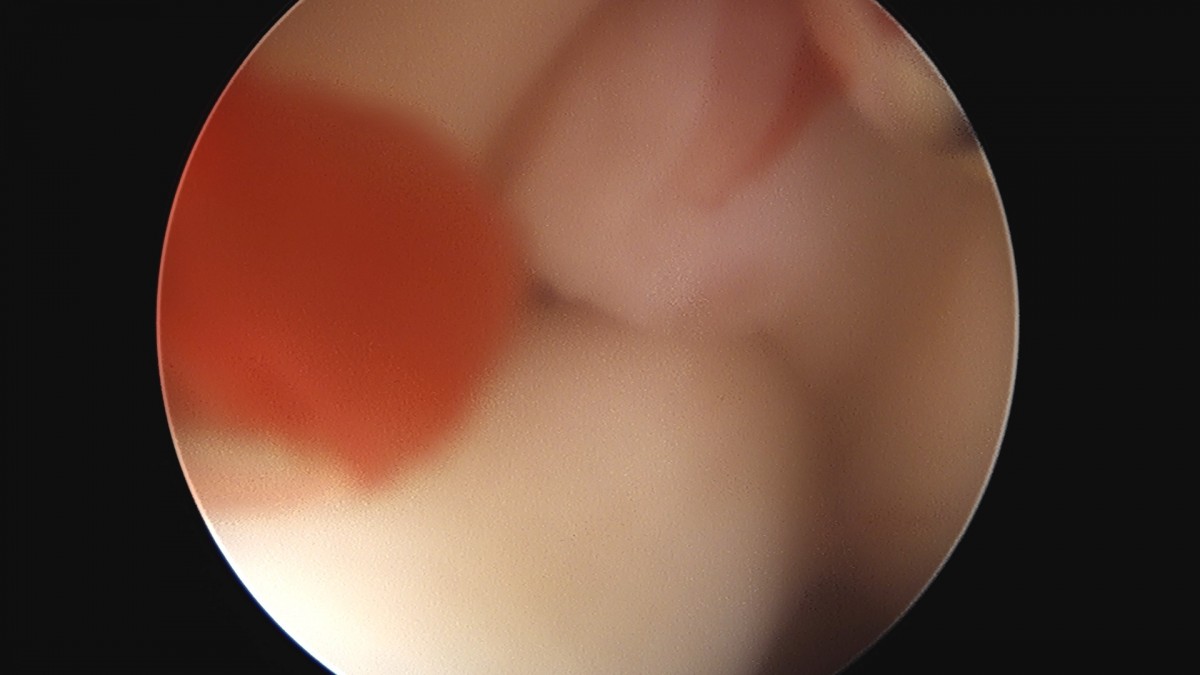

이재상원장님 어깨 견봉하 감압술 김선O 환자

작성자 최고관리자 댓글 0건 조회 823회 작성일 25-09-16 15:27